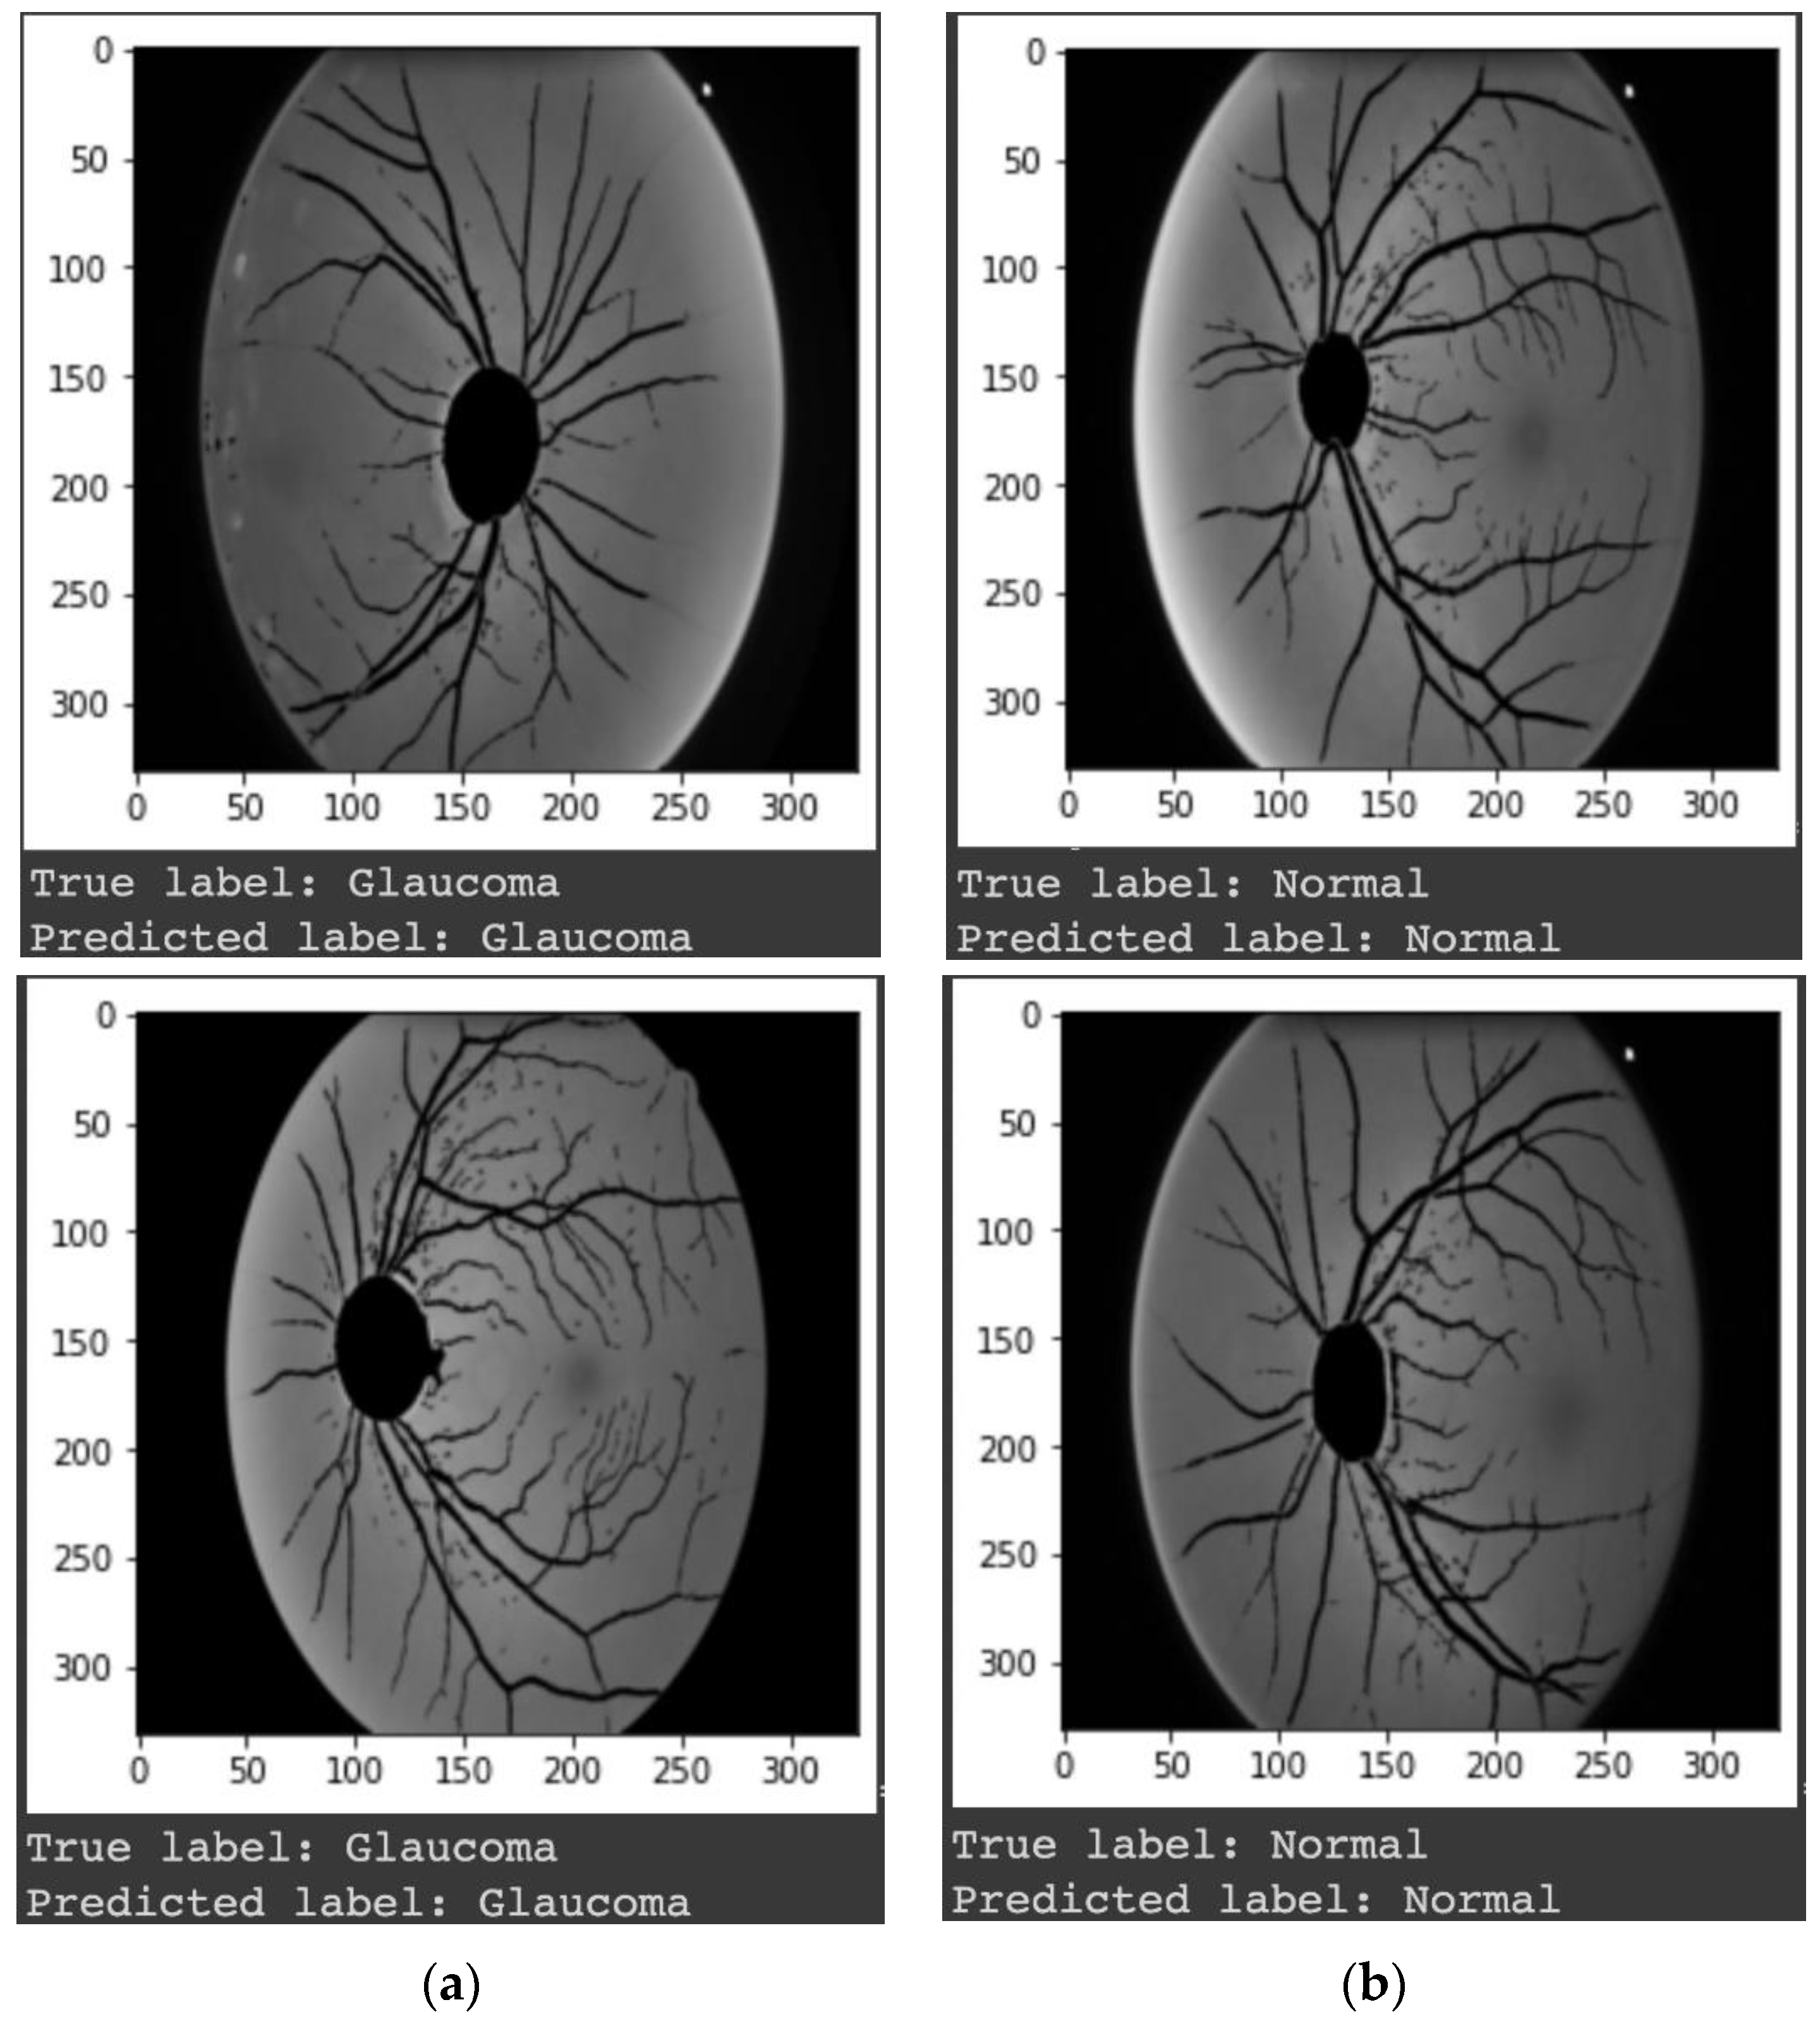

- (i)

- We proposed an alternative way to detect glaucoma disease by analyzing the damage to the retinal nerve fiber layer (RNFL). Our proposed method consists of novel step-by-step preprocesses to extract RNFL features from digital fundus images.

3. Results

4. Discussions